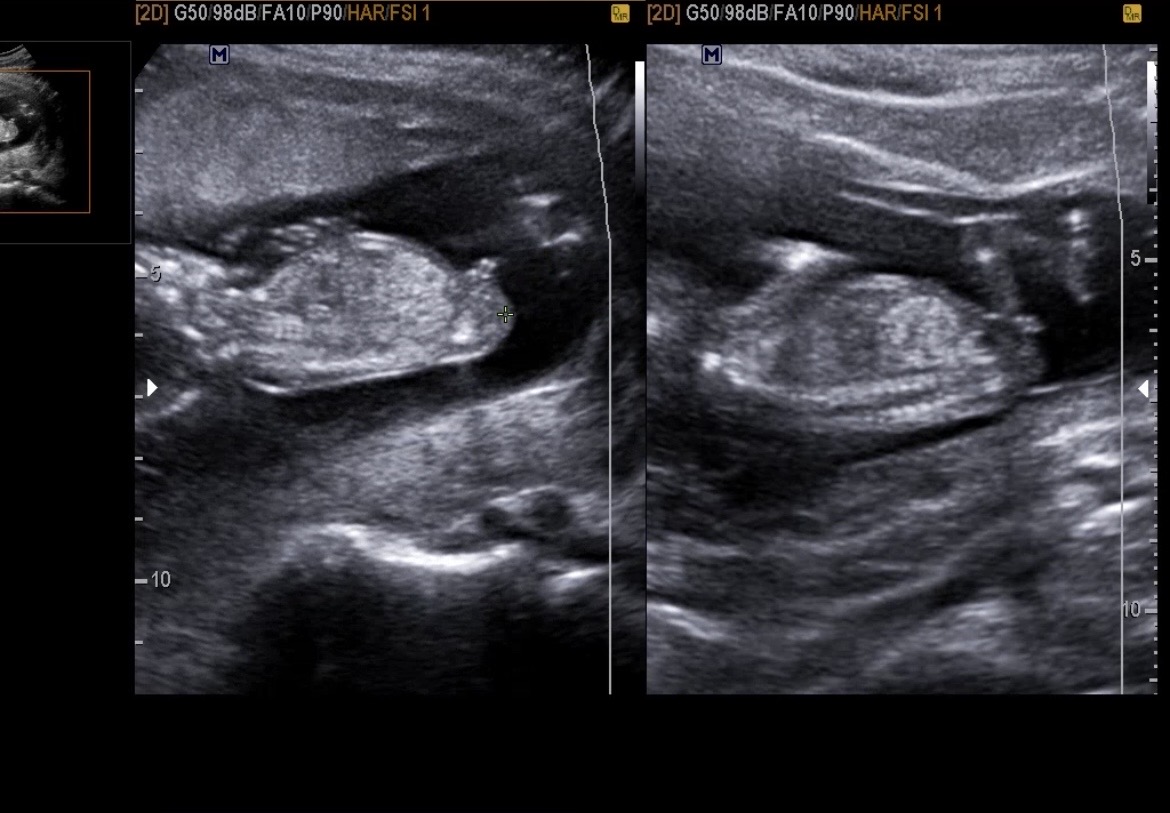

13주 0일 각도법 봐주세요 🫶🏼

쌍둥이들 각도법 봐주세여 🙏 오늘 원장님은 왼쪽-아들/오른쪽-딸이라고 하셨는데 지피티랑 빌리ai는 둘 다 딸같다고..🤣🤣